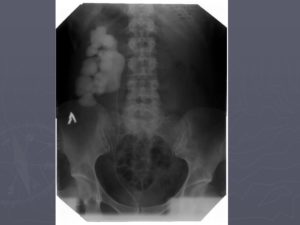

Обзорная урография позволяет выявить тени камней, очертания поясничных мышц, структурные отклонения в мочевыделительных органах и пр. Экскреторная урография помогает точно обнаружить аномалии и патологии чашечно-лоханочных структур.